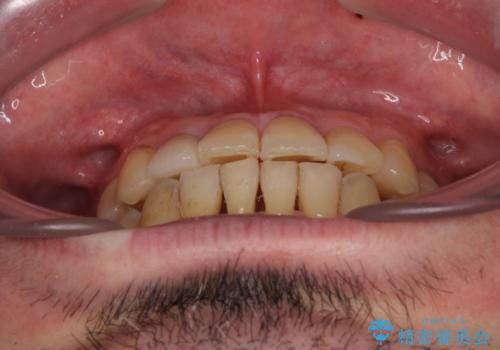

- 奥歯の痛みと前歯のデコボコを気にして来院された患者様です。

左右下顎の大臼歯は、ともに歯根が破折しており、抜歯が必要な状態でした。

咬み合わせは受け口傾向であり、上顎前歯の叢生が顕著であったことから、第1小臼歯抜歯による矯正治療も検討しましたが、下顎大臼歯を左右ともに抜歯するため、非抜歯による矯正治療を行うこととしました。